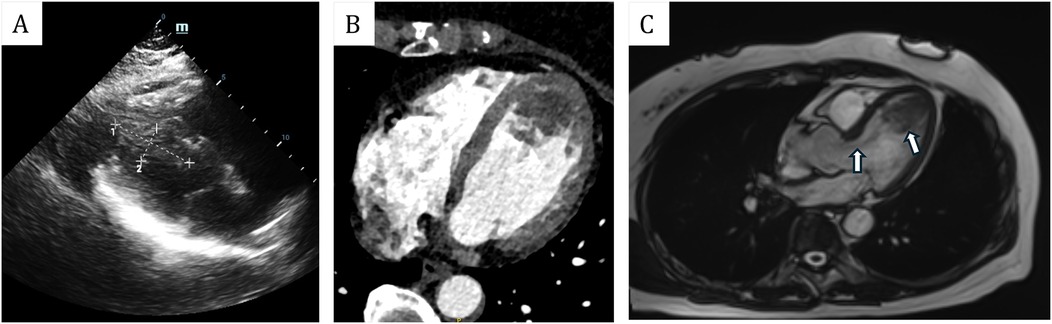

Figure 2

(A) Transthoracic echocardiogram showed that the mass was located in the left ventricle, measuring approximately 49 mm × 21 mm. (B) Enhanced cardiac computed tomography (CT) revealed an irregularly shaped patchy filling defect within the left ventricle. (C) Magnetic resonance imaging (MRI) revealed that the mass was situated in the left ventricle, with its pedicle attached to the ventricular septum. Additionally, flocculent materials were observed extending from the main body of the mass to the aortic valve orifice.

A 61-year-old female patient presents with a medical history characterized by multiple neoplasms and surgical interventions. Initially, in 2006, she underwent a subtotal hysterectomy due to uterine fibroids. A decade later, in 2016, bilateral breast nodules were detected. Ultrasonography revealed a 13 mm × 6 mm nodule in the left breast and a 14 mm × 8 mm nodule in the right breast. Subsequently, she underwent a Mammotome excision of the bilateral breast masses under local anesthesia and B-ultrasound guidance. Postoperative histopathological analysis identified high-grade ductal carcinoma in situ in the left breast and fibroadenoma in the right breast. Consequently, a left breast-conserving radical mastectomy was performed. The postoperative specimen revealed no residual carcinoma, and axillary lymph node dissection showed no evidence of metastasis. Three months following the breast cancer surgery, the patient was readmitted for postoperative adjuvant radiotherapy, receiving a cumulative radiotherapy dose of 60 Gy over 30 fractions. Subsequent outpatient follow-ups indicated no recurrence of breast cancer. In 2023, the patient was hospitalized due to bilateral lower extremity numbness. At that time, she reported no symptoms of chest tightness, dyspnea, cough, or expectoration. A computed tomography angiography (CTA) of the lower extremities revealed an occlusion of the right popliteal artery, along with severe stenosis in the right external iliac artery, proximal right femoral artery, and proximal right deep femoral artery. Echocardiography did not detect any cardiac space-occupying lesions at that time. The patient underwent a thrombectomy of the popliteal artery in both lower extremities, postoperative pathological analysis identified the thrombus as a mixed thrombus (Figure 1A). In 2024, the patient was readmitted to the hospital due to weakness in the left lower extremity and reduced skin temperature, without any heart symptoms. CTA of the lower extremities indicated thrombosis and severe stenosis in the left common iliac artery, external iliac artery, and internal iliac artery. Subsequently, she underwent a left iliac artery thrombectomy. Postoperative pathology confirmed a diagnosis of myxoma (Figure 1B). Subsequent echocardiographic examination identified a slightly hyperechoic mass in the left ventricle, measuring approximately 49 mm × 21 mm, characterized by well-defined boundaries yet of indeterminate nature. Associated with this mass were flocculent structures extending to the aortic valve orifice, oscillating with the blood flow (Figure 2A). Enhanced cardiac computed tomography (CT) revealed an irregularly shaped patchy filling defect within the left ventricle, indicative of a potential thrombus or neoplasm (Figure 2B). Cardiac magnetic resonance imaging (MRI) further identified a space-occupying lesion in the left ventricle, raising the possibility of a neoplastic lesion, such as a myxoma or vegetation (Figure 2C).